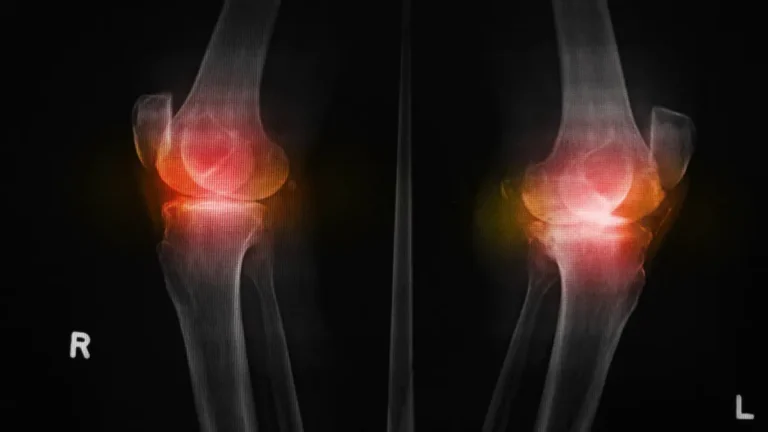

Osteófitos no joelho: causas, sintomas e tratamento

Receber um exame com o diagnóstico de osteófitos no joelho pode gerar preocupação. O termo popular “bico de papagaio” costuma assustar, mas é importante saber que, embora exija cuidado, essa alteração é uma resposta natural do corpo e pode ser…